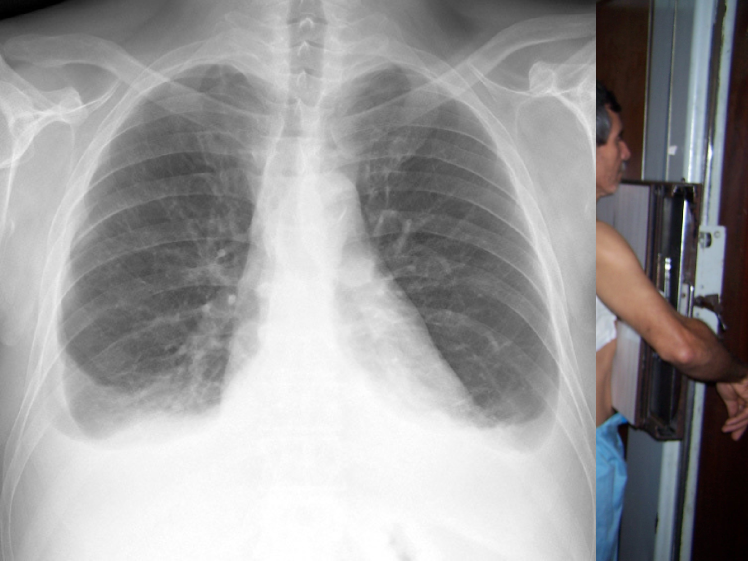

In addition to the standard DICOM metadata, the information on image projection and radiographic positioning was extracted. These data were found in different DICOM fields in non-structured free text (Position View, Patient Orientation, Series Description and Code Meaning). The projections principally identified after excluding obliques were antero-posterior (AP), postero-anterior (PA) and lateral (L). The different body positions were erect, either standing or sitting, decubitus or lying down, supine or lying on back, lateral decubitus right lateral and left lateral. In addition, different protocols were identified based on different clinical scenarios: standard standing PA and L, mobile x-ray (for patients unable to stand) in either AP erect in bed or AP supine, pediatric protocol for patients up to 3 years old, lordotic views, ribs and sternum modality views.

Refer to caption

(a) P-A

(b) Lateral

(c) Lordotic

(d) A-P supine

(e) A-P

(f) P-A

(g) Lateral

(h) Lordotic

(i) A-P supine

(j) A-P

Figure 2: Common chest x-ray projections.

The projection information is highly relevant for diagnosis. For example, AP views, which are commonly used in pediatric patients, show an enlarged heart silhouette (Fig. 2(j)) that should not be interpreted as cardiomegaly, but merely the expected large-depth ratio of reversed organ observation (Fig. 3). Another illustrative example is the distinct pattern that pleural effusions have in the standing position (Fig. 4(a)), in which a typical meniscus sign is commonly found as opposed to decubit projections (Fig. 4(b)). Given that the number of different projections is unbalanced (for instance, PA followed by lateral projections typically comprise the majority of chest x-rays), there is the risk that none of the other projections will have sufficient instances with which to train models capable of discriminating pathological from non-pathological patterns in the context of the projection.

There are particular radiological landmarks that differentiate projections, which radiologists are trained to identify. For instance, in the case of PA projections, these landmarks are the presence of air in the gastric chamber and the scapulae projected outside the lung fields. Although these features can be learned, models trained in unbalanced datasets with a poor representation for different projections may not have sufficient instances to properly learn those patterns. An illustrative example is when the heart enlargement in AP projections is attributable only to the effect of the projection, while the trained model erroneously predicts cardiomegaly.